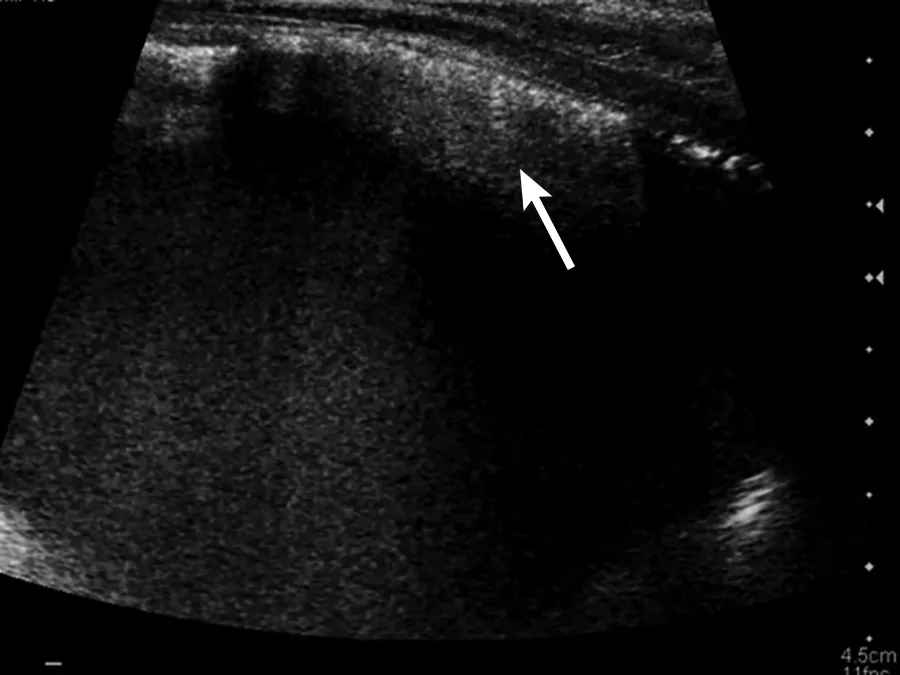

Cystitis is generally a diagnosis of exclusion, especially in cats with hematuria or difficulty urinating (ie, stranguria). Sterile and bacterial cystitis cannot be differentiated on ultrasound, and cystocentesis is needed to further characterize sediment even if hyperechoic foci are identified. The urinary bladder wall may be mildly thick or irregular on the luminal side (Figure 1). When measuring the wall of the urinary bladder, a representative region should be selected and the measurement made from the bladder mucosa to the serosa layer. Care should be taken to remain perpendicular to the wall, not to the ultrasound probe, to minimize measurement enlargement that can occur with obliquity. Overall measurement is more important for repeat evaluation to determine whether the urinary bladder is increasing or decreasing in size; retaining a consistent amount of urine (or catheterizing the patient and adding sterile saline) can help ensure consistent measurements.

Sagittal image of the urinary bladder with a diffusely thick wall due to cystitis. Left, cranial; bottom, dorsal